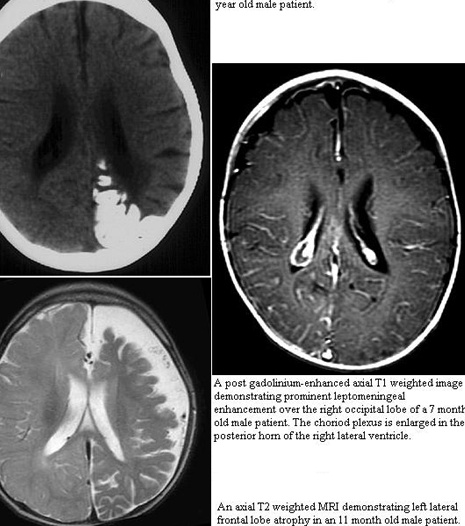

MRI with contrast will reveal the presence of the leptomeningeal capillary-venous malformation and the extent of involvement with brain structures.